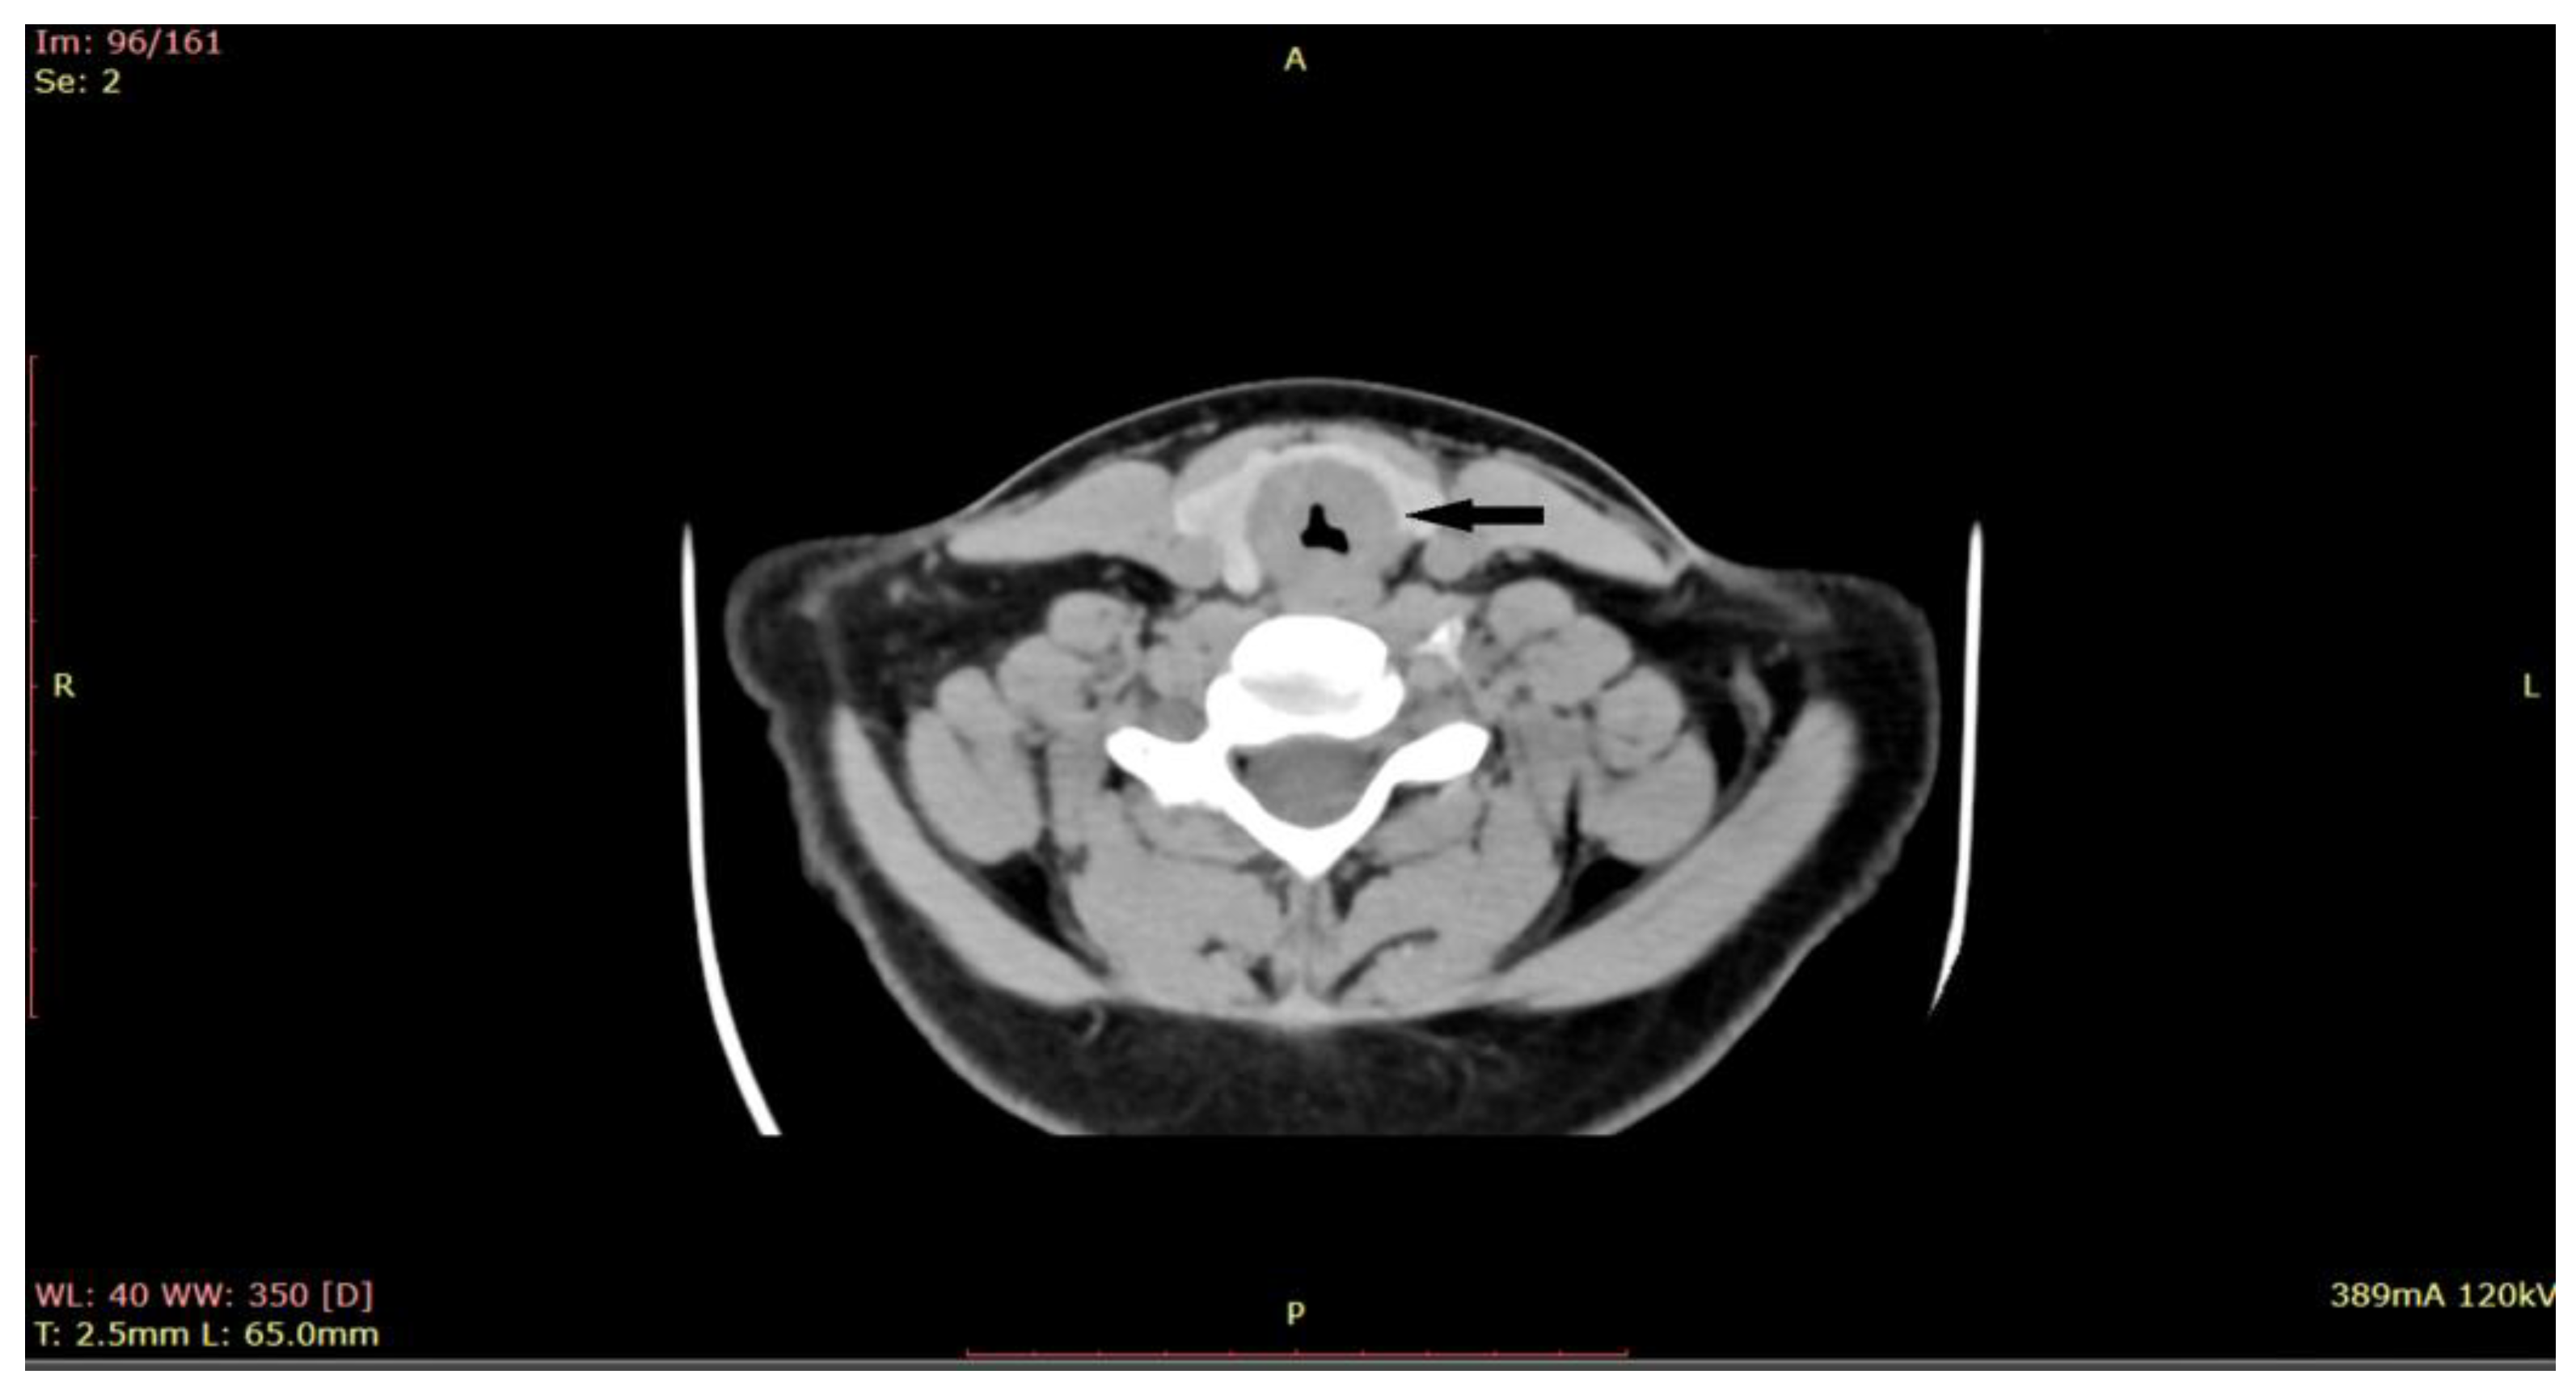

Given the critical nature of the patient’s condition, an immediate intervention was performed before sending the patient for a CT scan. Emergency tracheostomy was performed to secure the airway. However, during the operation, the patient developed a spontaneous left pneumothorax, which necessitated pleural drainage. The aim of the procedure was to secure the airway, relieve respiratory distress, and obtain a biopsy for further diagnosis. Once the patient’s condition stabilized after the pleural drainage, a biopsy of the subglottic tumor was obtained through direct laryngoscopy. During the direct laryngoscopy procedure, a tumor formation was observed in the subglottic region, involving the first tracheal ring. On examination, the tumor appeared slightly indurated, with smooth local mucosa. It circumferentially covered the subglottic area with marked narrowing of the respiratory space. A computed tomography (CT) scan was performed (Figure 2), which showed subglottic mass involving the trachea, with marked circumferential and slightly asymmetrical thickening of the laryngeal walls, from a plane passing through the arytenoid cartilages, involving the cervical trachea until the distal space C7-T1, with marked intraluminal stenosis (71%) and compression of the thyroid lobes.

Figure 2. CT of the larynx shows a subglottic submucosal mass with marked intraluminal stenosis (at the arrow)-axial plane.